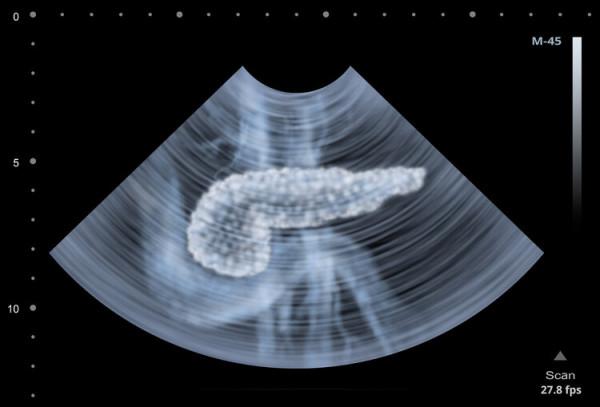

腹部CT檢查提示胰腺出現明顯水腫,有廣泛炎性滲出;甘油三酯高達74.93mmol/L(正常值的44倍),脂肪酶1522U/ml,確診為急性高脂性胰腺炎。

通常情況下,首先要做上腹部磁共振(MRI)和上腹部CT增強檢查,明確胰腺是否充血、水腫或出血。其次,要做超聲檢查,明確膽總管或膽囊的結石情況。